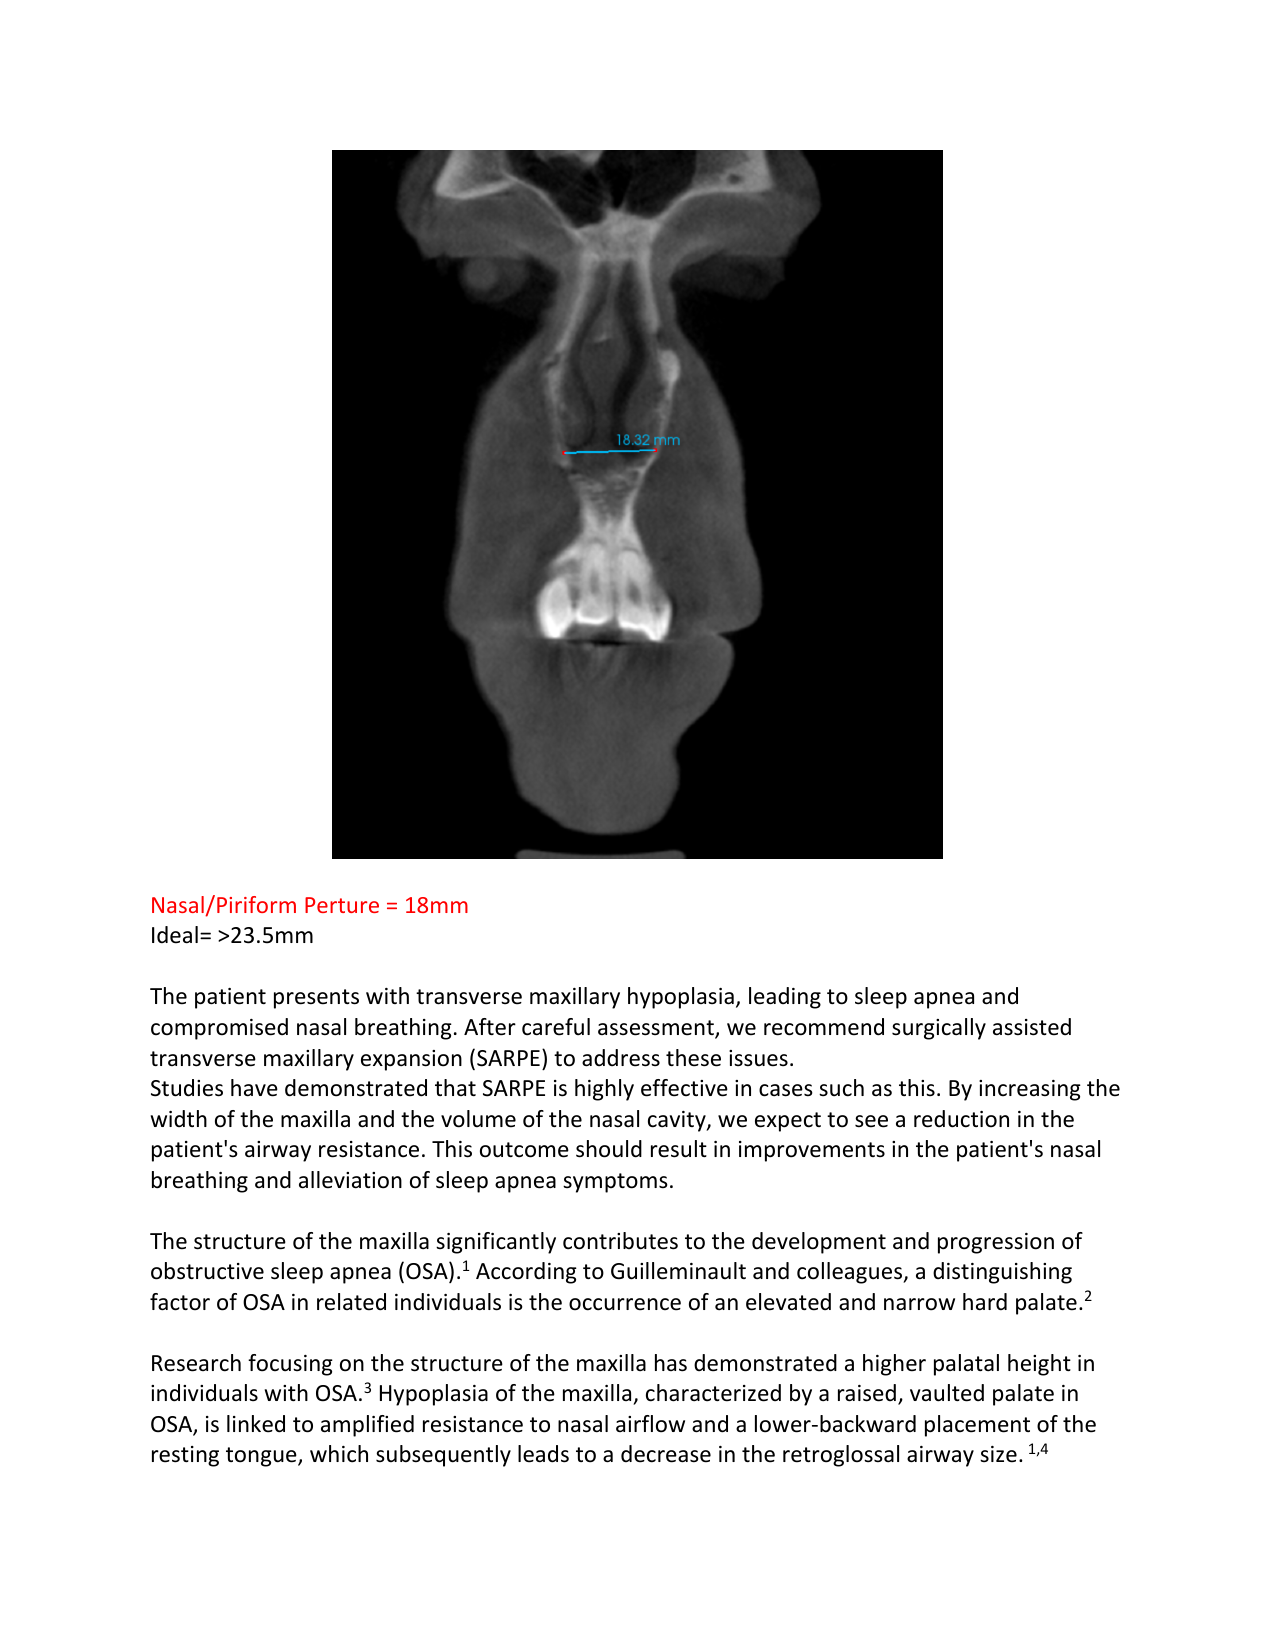

My jaws are severely underdeveloped (bimaxillary hypoplasia), my face is crooked due to a tilted upper jawbone (maxillary cant), and I have a posterior crossbite on both sides, which worsens my bite and facial imbalance. My palate is so narrow and high that my tongue is pushed backward and downward, making it hard to swallow and speak. It disrupts the whole balance of my body, and every time I swallow, my body has to compensate, which creates tension in my neck, jaw, and shoulders and affects my posture. I constantly have ear pressure and pain in my jaw joints, and together with my exhaustion, it’s almost unbearable.

I’ve had to breathe through my mouth my whole life because of my airway, which is as narrow as a straw. This affects my nervous system and leads to chronic stress, anxiety, brain fog and mental fatigue. I can barely sleep anymore because my body is stuck in a constant state of fight-or-flight, never able to rest. Even after trying sleeping pills and a CPAP machine, the problems remain.

To get the help I need, I now have to seek care in the US, where I can have advanced jaw surgery. This includes a DOME procedure, where the upper jaw is widened by separating the bone in the midline and lifting the narrow palate to create space for the tongue and improve the airway. I will also need double jaw surgery to correct the position of my jaws and restore balance to my face and body. These procedures are not without risks, but without them, I don’t have a life. I am surviving, but I am not living. I’ve already saved and borrowed as much as I can, but it’s not enough. That’s why I’m asking for your help. If you can contribute to my surgery, I would be deeply grateful, no matter the amount. The money will go toward the remaining surgical costs, essential preparations, aftercare, braces, and travel expenses. I would also be thankful if you would consider sharing my story with others who might be able to help.